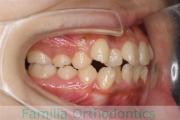

- ≫治療前

上顎

下顎

前歯の関係など

右側

正面

左側